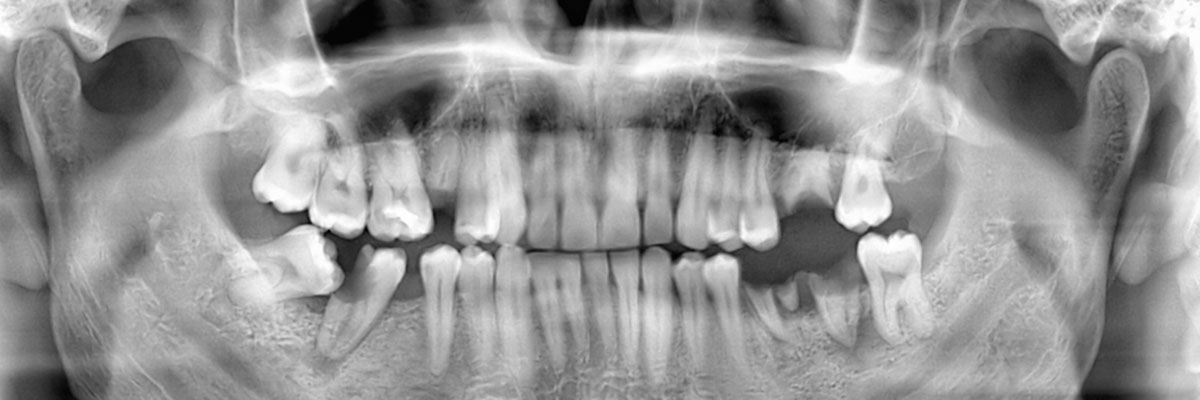

You may need a wisdom teeth extraction at some point in your life. It is rare for a person to have enough room for all of their wisdom teeth, and as a result, they tend to grow in impacted. This can be uncomfortable, pushing your other teeth forward and creating a space for food to become trapped; it can also increase your risk of infection and decay. This is why we often recommend that our patients have their wisdom teeth removed. When you schedule an appointment with City Centre Dental, we can examine you, take X-rays, and let you know if and when you should schedule an extraction procedure. You can reach us by calling (248) 423-9393.

At City Centre Dental, we understand that each of our patients is unique and so are their teeth. Whether or not you need to have your wisdom teeth removed by a dentist, will really depend on the size of your palate. If you have plenty of room for all of your teeth and your third molars, they can stay in place. There is no point in removing something that grows in straight and is healthy. However, any tooth that grows in impacted needs to be removed because it is posing a direct threat to your other teeth and roots in addition to being a target for infections. The best way to find out if your wisdom teeth should be removed is to call 248-423-9393 and schedule an appointment with our Southfield dentist office. We can make a recommendation and answer any other questions you have about the procedure itself.